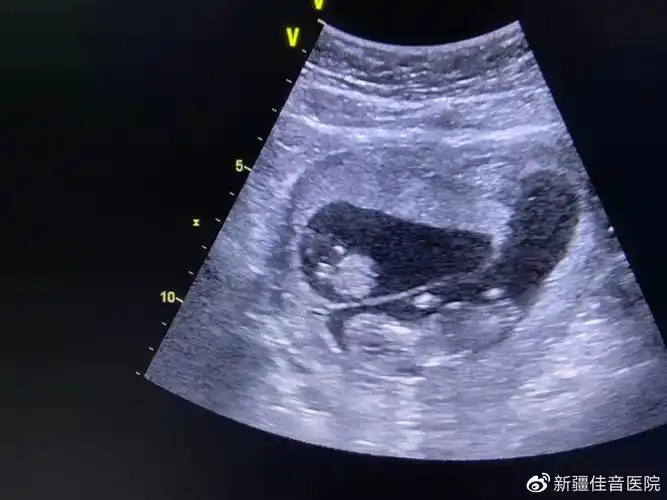

双胞胎b超图50天显示,这个正常吗?

双卵双胞胎是不是龙凤胎几率很大,这个是今天的b超图怀孕50来天!

双胞胎后续来啦,单绒双羊,顺利8周 前两天做了b超,查了是单绒双羊~也

双胞胎移植40天